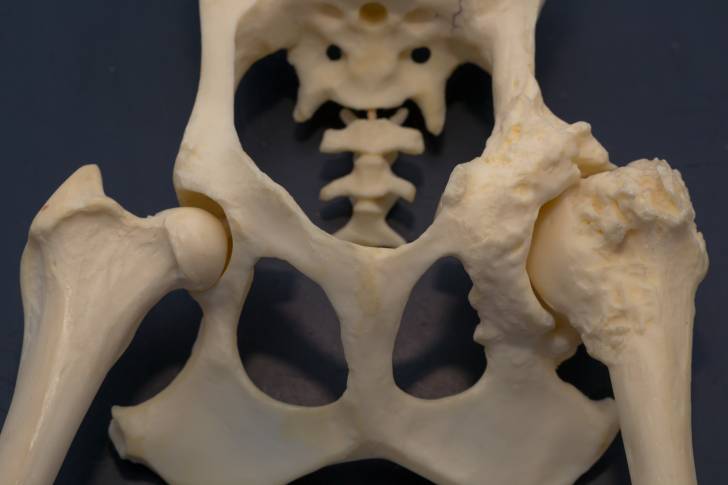

La dysplasie coxo-fémorale, communément appelée dysplasie de la hanche, est une maladie articulaire qui finit par causer à terme des problèmes invalidants pouvant aller jusqu'à une paralysie complète de la patte touchée. Elle est due à une malformation des os qui forment l'articulation, ou bien à une défaillance du ligament qui relie le fémur au bassin. Elle est le plus souvent bilatérale, c'est-à-dire qu'elle touche les deux hanches.

Chez le chien, la dysplasie coxo-fémorale est causée par une malformation au niveau de la hanche, qui peut elle-même prendre trois formes différentes :

Dans les trois cas, ces anomalies provoquent des mouvements anormaux qui avec le temps engendrent une déformation du fémur et/ou de la cavité articulaire, et donc une dysplasie de la hanche.